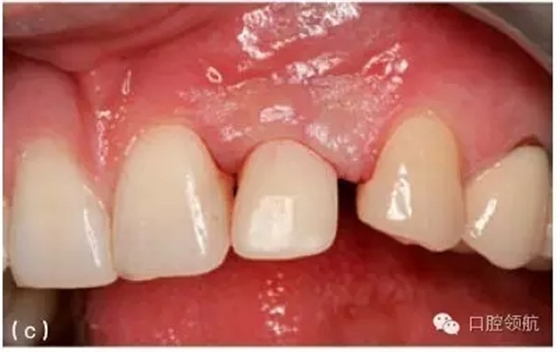

如上所述,有些情況下,種植體位置不正或傾斜是無法避免的。從這方面來看,如果種植體成角度植入,額外的根向深入可以提供充足的操作空間,使得修復(fù)體形態(tài)可以平緩過渡。例如,在上頜前部牙槽嵴,雖然有足量的骨質(zhì)來容納一個(gè)種植體,但是,為了避免存在倒凹區(qū)的唇側(cè)骨板穿孔,種植體必須以一個(gè)比預(yù)想更大的角度植入。種植體增加的角度,可以通過角度基臺(tái)矯正。這時(shí),植入深度的增加,使傾斜角度的矯正更加平緩,并且形成更加合理的牙體形態(tài)(圖9.31a~c)。然而這個(gè)技術(shù)并不是萬能的。在彌補(bǔ)種植體傾斜方面仍存在

限制,尤其在糾正植入位點(diǎn)不良的種植體上存在一定困難。

圖9.31 (a)對(duì)于深覆患者,當(dāng)種植體植入角度偏頰側(cè)的時(shí)候,要相應(yīng)增加植入深度,以避免下頜牙切緣與種植體接觸;增加操作空間,有利于形成逐漸過渡的修復(fù)體穿齦外形。(b)從種植體平臺(tái)到修復(fù)體頸部,逐漸過渡的臨時(shí)冠軸面外形。(c)臨時(shí)冠就位的臨床觀,在美學(xué)區(qū)域,對(duì)于非手術(shù)式的組織塑形,推薦2~3個(gè)月的塑形時(shí)間。